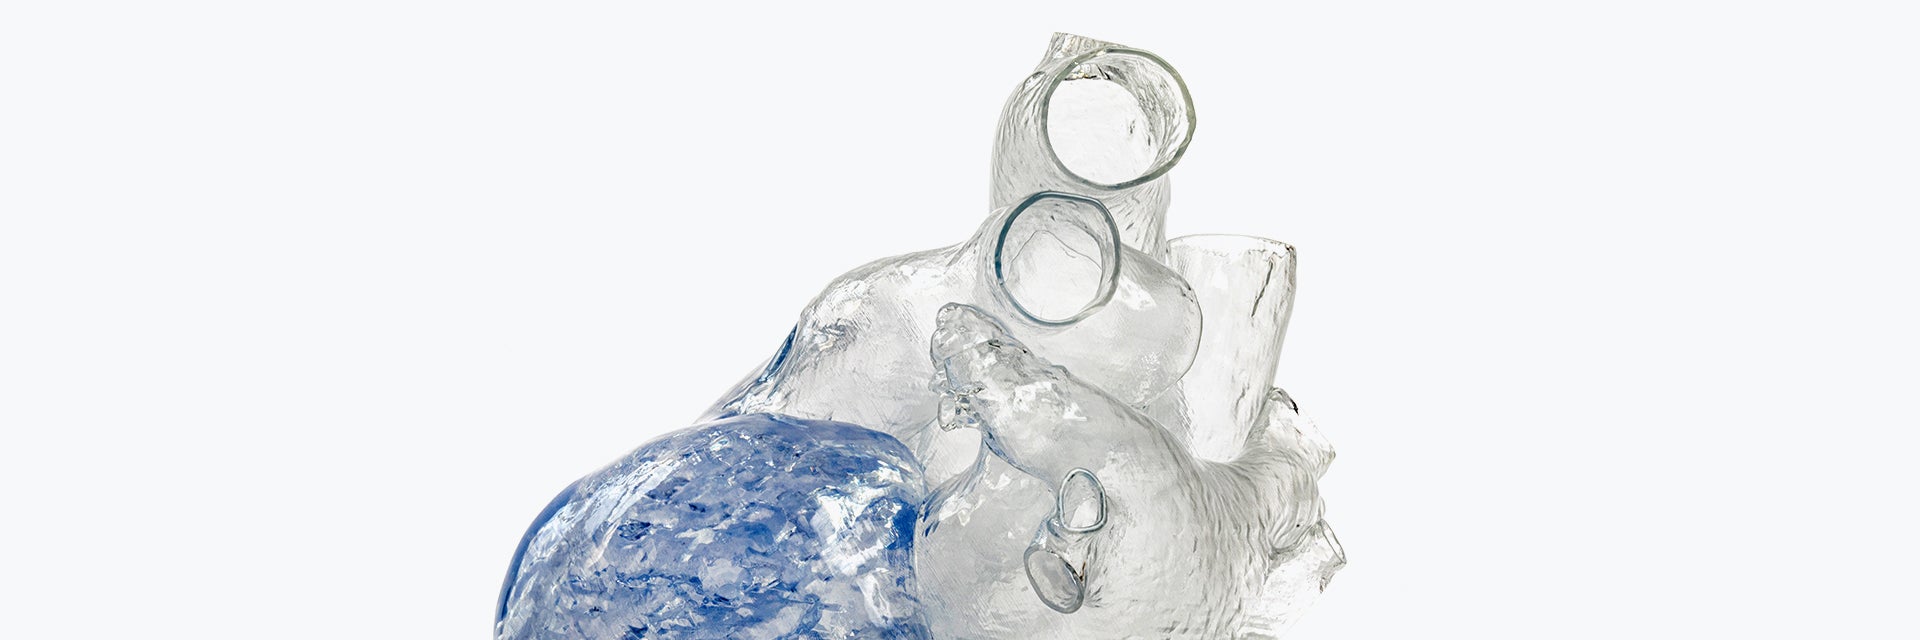

In the next step, Fritschi et al. performed a virtual fitting of the current artificial heart design to each of the individual patients’ 3D models (Figure 3). This virtual fitting is an accurate and cost-effective way to determine the precise device fit and reveal areas for improvement.

Figure 4 shows an overlay of the CAD model of the artificial heart on a patient’s heart. The alignment could also be verified using the original image data (Figure 3), which allowed the authors to iteratively improve the device design.

Figure 3 and Figure 4